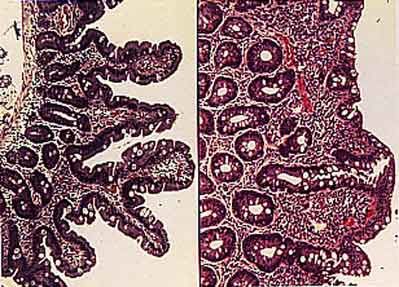

Figure 3 Villi Atrophy (image from Dr. David Elliot, permission pending)

Hematoxylin-eosin stained cross-sections of intestinal villi: normal epithelium (left) and celiac epithelium (right), characterized by infiltration of intraepithelial lymphocytes and flattened villi.